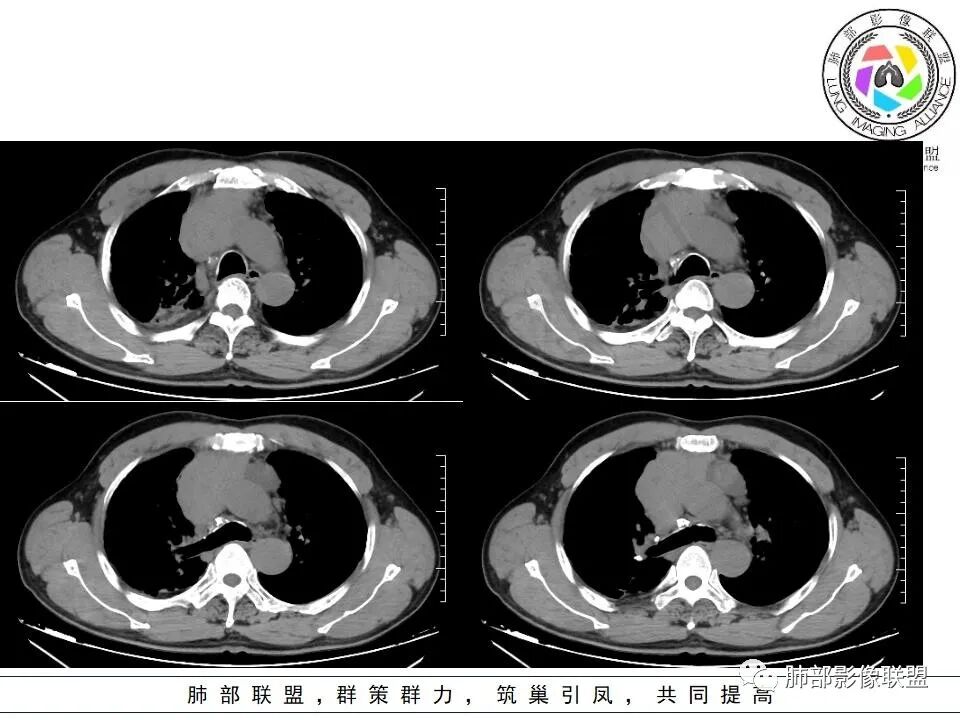

▲上腔静脉内瘤栓

▲病灶骑跨在主动脉前缘,主动脉包绕

下面没提及右心房,估计没累及。

▲左侧边缘有强化的病灶,似乎符合坏死或囊变、或有粘液类物质。内部似有裂隙、坏死。坏死边界偏清。

▲右上叶、下叶胸膜下为主的斑片实变影,局部结构变形。支气管后移。支持慢性炎性病变,结核可能。从这个角度分析:纵隔肿瘤与肺部病灶关系不密切。

2.上纵隔增宽并见不规则块影,密度不均,轻度不均匀强化,隐约见液化密度区。

病灶边界不清,轻度分叶,后方部分紧密包绕升主动脉且侵入上腔静脉及左无名静脉末端,相应上腔静脉及左无名静脉管壁不完整。

3.右肺上叶体积缩小并见边界较为清楚的条片影及结节影,密度较高且不均,期间显示支气管扩张。

4.右肺门及纵隔见钙化淋巴结。

5.双侧胸腔未见积液。